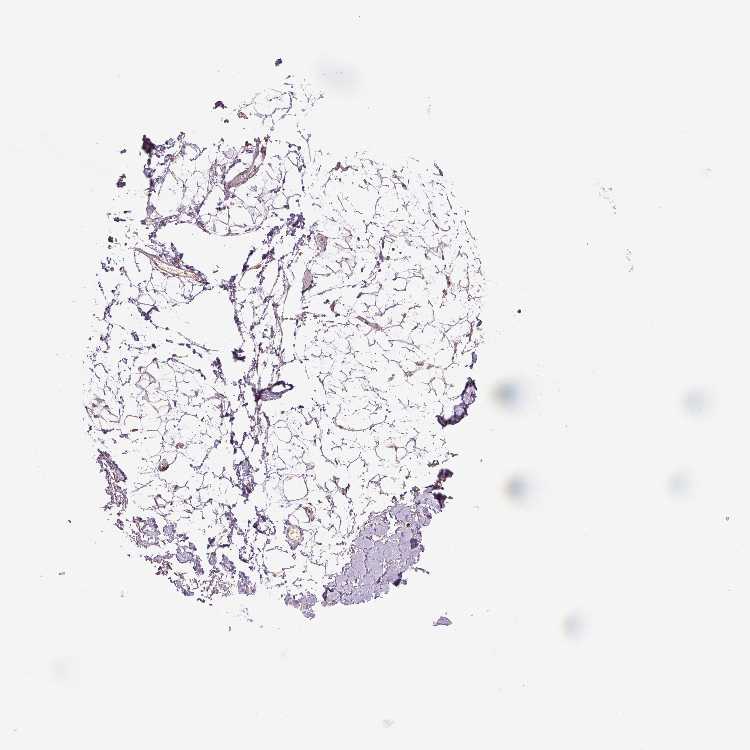

Adipose tissue